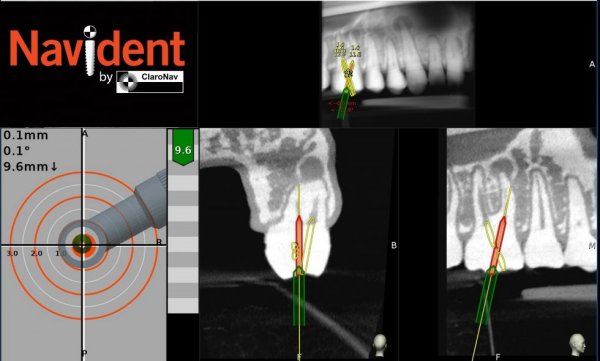

The most exciting new application of Navident is in the field of endodontics where it provides guidance for complex root canal treatments and microsurgery. For root canals Navident enables drilling small holes to reach narrow, highly calcified canals, instead of ruining crowns in repeated attempts to reach a tiny canal opening deep in the tooth. Jason Pardo, ClaroNav’s VP Sales and Marketing, commented: “Navident enables carefully evaluating, planning and navigating root canal treatments and apicoectomy procedures with minimal invasiveness. This shortens chair time and reduces the number of patient appointments needed. Beyond the obvious benefits to convenience and efficiency, this reduces the likelihood of cross infection between patients and dental staff, an issue made critical by COVID that will likely remain critical in years to come.”